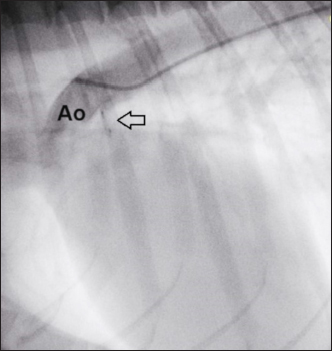

The stability of the device was subsequently tested with the push–pull “Minnesota wiggle” maneuver, and the cessation of transductal flow and the correct positioning of the device was verified using TEE (Figs. 4 and 5). The device was then deployed by rotating the delivery cable counterclockwise with the appropriate plastic vise. To verify the closure of the PDA and the absence of protrusions in the aorta further, a second angiography was performed as before (Fig. 6).

Fig. 6. Angiography conducted after device (arrow) release. The PDA is completely occluded and no residual shunt is visible.